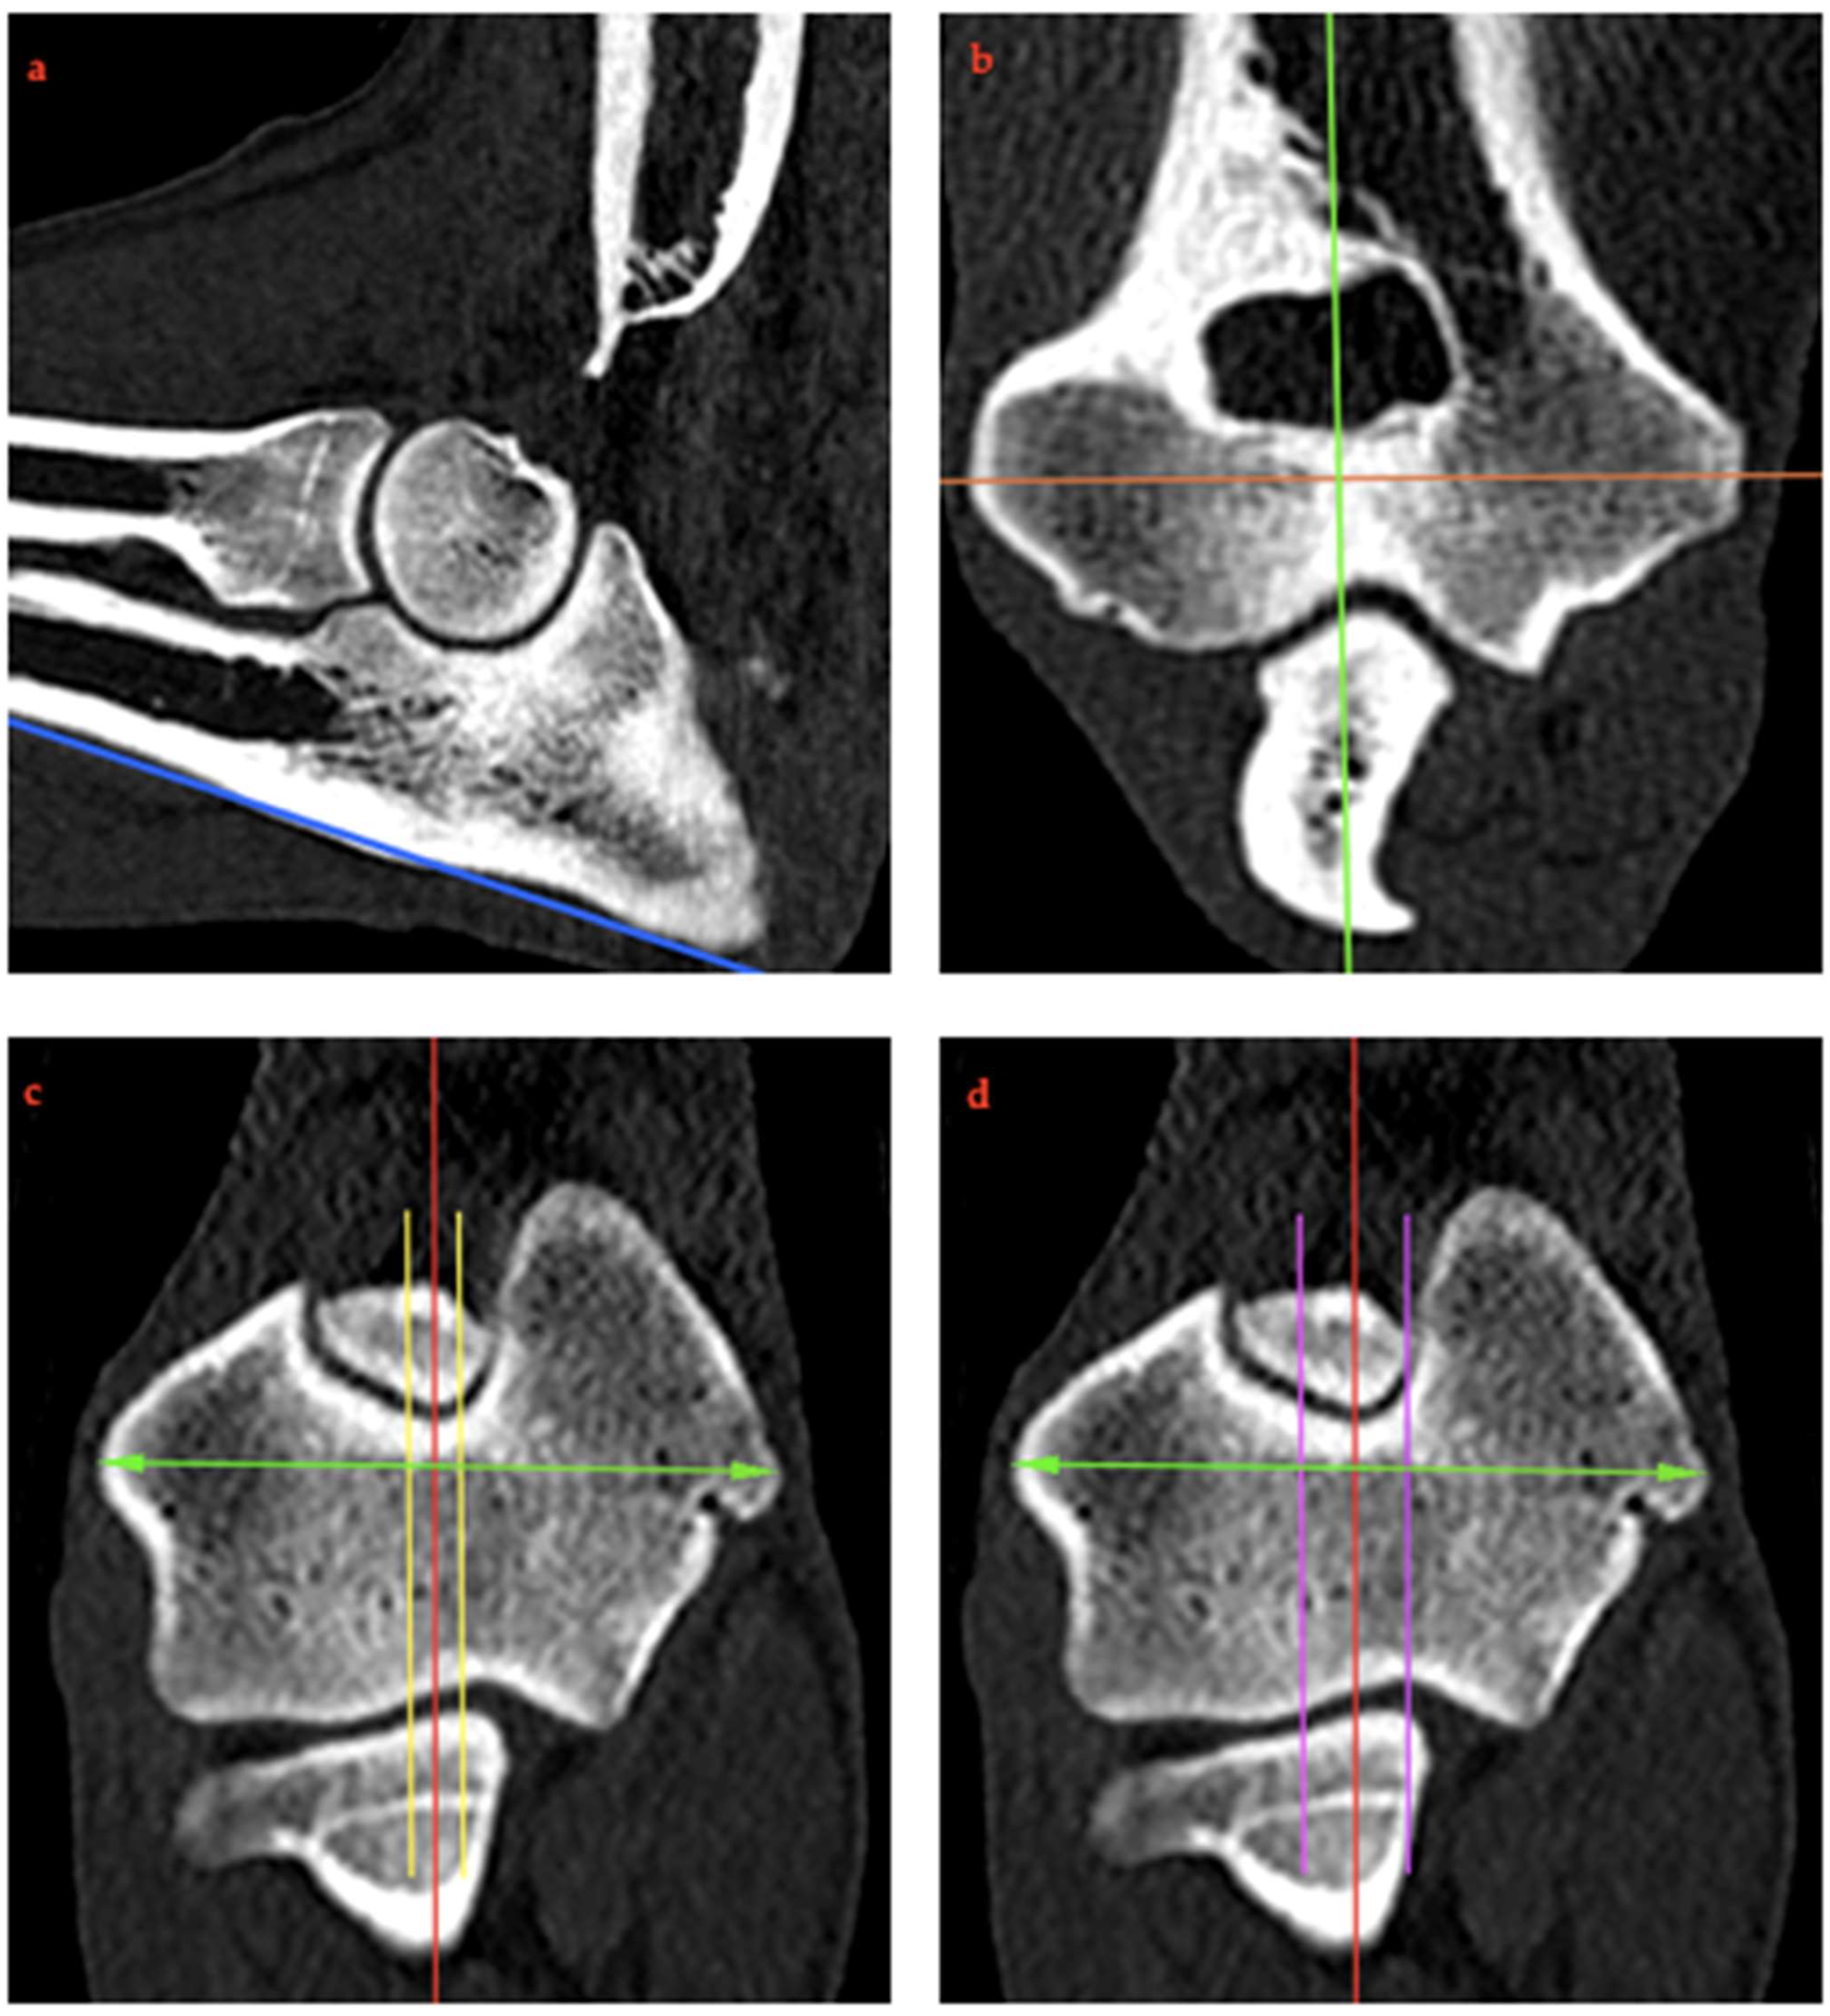

2.4. RUI Measurements